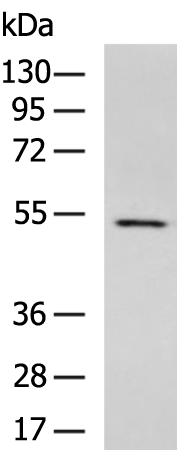

分类: 科研抗体货号: P10185别名: PROLIDASE应用: WB,IHC反应种属: Human, Mouse, Rat